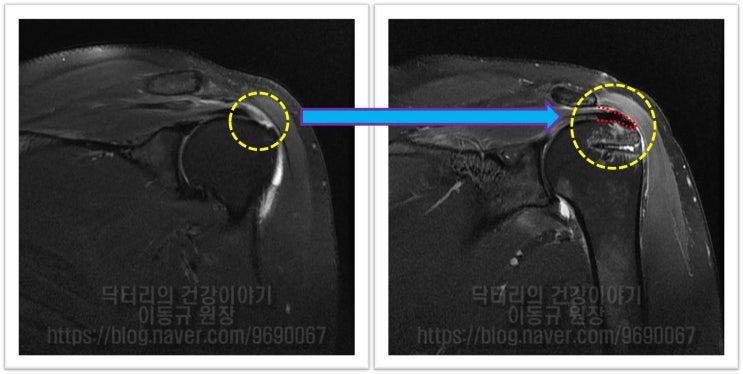

MRI 상 파열 사이즈도 크지 않고 힘줄 상태로 그렇게 나쁘게 보이지 않습니다. 관절경을 통하여 봉합술을 하기로 하였습니다.

이 환자의 경우 나이가 비교적 젊음에도 불구하고 힘줄의 상태가 매우 좋지 않았습니다. 아마 수년간 통증주사(아마도 스테로이드)만 맞고 팔을 계속 사용하면서 회전근개 손상은 점점 진행되고 퇴행성 변화가 가속화 된 것으로 사료됩니다. 수술 후 6주에 MRI 검사를 시행하였습니다.